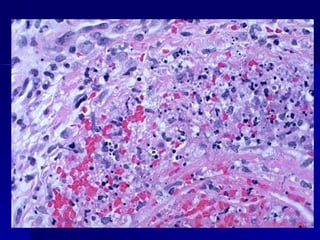

Inflamación aguda. Se aprecian PMN densamente agrupados con núcleos multinucleados

Inflamación aguda. Seaprecian PMN densamente agrupados con núcleos multinucleados

Exudado necrótico en un absceso hepático amebiano

Exudado necrótico enun absceso hepático amebiano